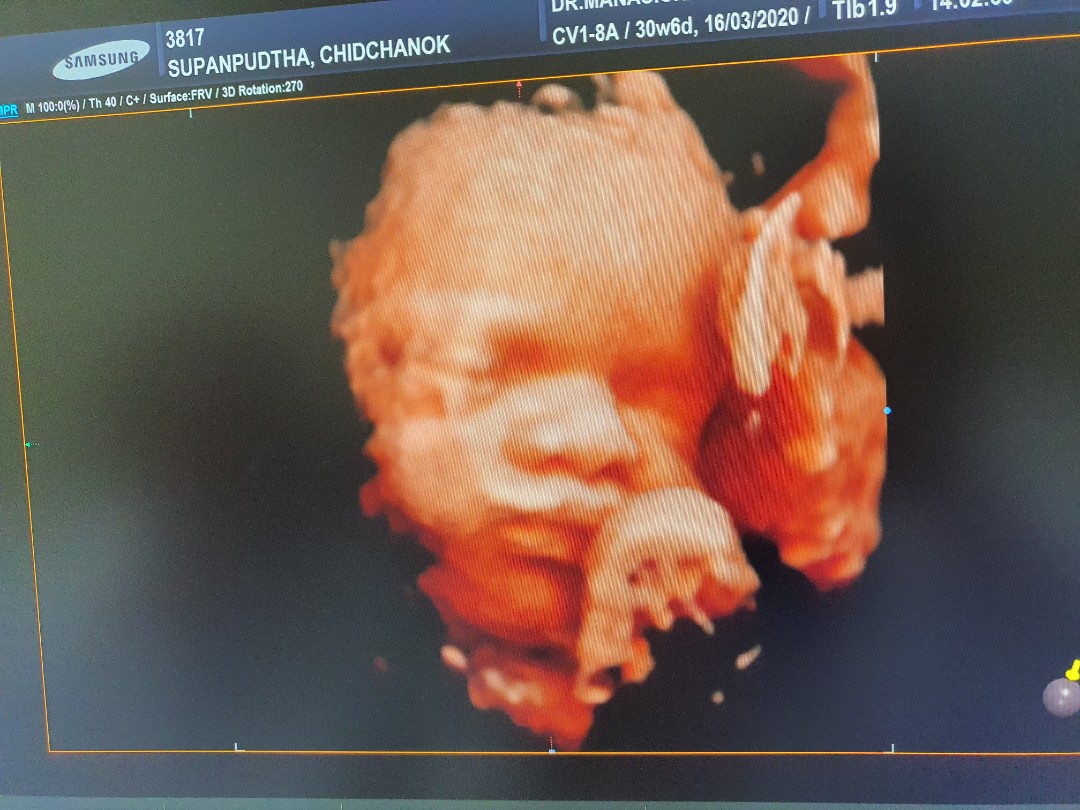

ขอดูรูปซาวของแม่ๆหน่อยค้าว่าได้ผู้หญิงผู้ชาย บ้านนี้ผู้ชายจ้าา

ญ จ้า